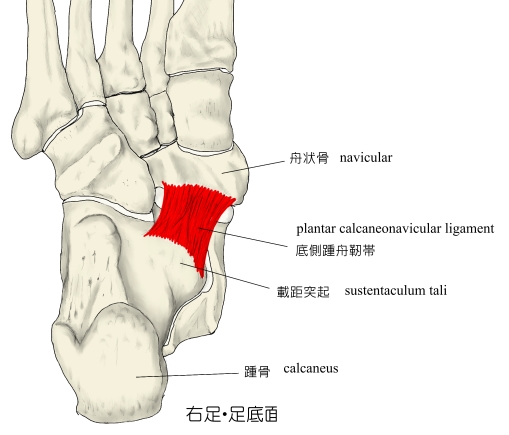

この3つのアーチ構造を維持するために受動的支持組織と能動的支持組織も大事な要素となります。

受動的支持組織とは、足底腱膜と底側踵舟靭帯で構成されていて、

- 底側踵舟靭帯=内側縦アーチの要である距骨頭部を支えています